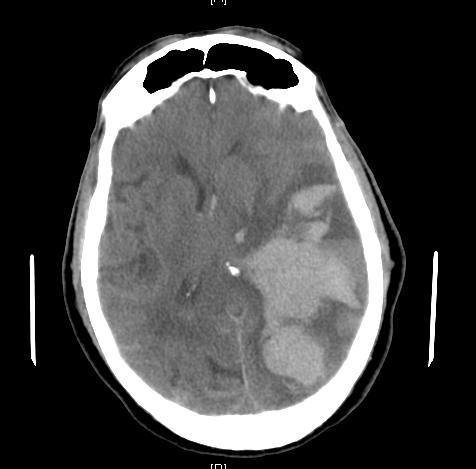

뇌탈출은 뇌 조직이 두개골 내에서 비정상적으로 이동하는 심각한 상태로, 뇌부종, 혈종, 뇌졸중, 뇌종양, 중추신경계 감염 등이 원인이다. 뇌탈출은 발생 부위와 방향에 따라 여러 유형으로 분류되며, 해마, 중심성, 대상회, 두개골, 중뇌덮개, 소뇌편도 등의 탈출이 있다. 증상으로는 비정상적인 자세, 의식 저하, 동공 변화, 구토, 두통, 발작, 쿠싱 삼징후 등이 나타나며, 뇌 기능 상실로 심혈관 및 폐 증상이 나타날 수 있다. 진단은 CT 스캔과 MRI를 통해 이루어지며, 치료는 원인 질환 제거와 감압 개두술을 포함한다. 뇌탈출은 심각한 장애나 사망을 초래할 수 있으며, 신경학적 회복의 예후는 좋지 않다.

뇌 탈출은 임상적 증상과 함께 CT, MRI 등 영상 검사를 통해 진단한다. 후두대공 헤르니아(대공헤르니아)는 소뇌 종양이나 출혈로 인해 천막 하강의 압력이 상승하고, 소뇌편도가 아래쪽으로 밀려나 대후두공(대공) 안으로 끼어든 상태이다. 천막상 병변이 진행되면 천막절흔헤르니아를 일으키고, 추가적으로 압력이 아래쪽으로 발생하기도 하므로, 가장 긴급한 처치가 필요하다.[1]